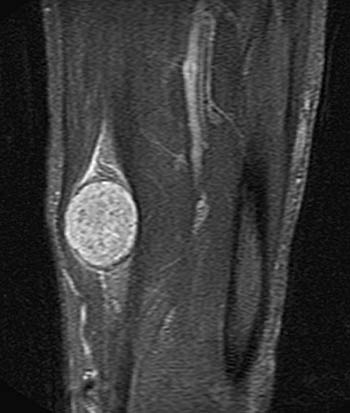

MR bu lezyonların tanısında en önemli tetkiktir. Özellikle ilaçlı MR ile sinir zerindeki kitle tam olarak görüntülenebilir. Bunun dışında Bilgisayarlı Tomografi ve Ultrasonografi de tanıda kullanılan önemli tetkiklerdir.